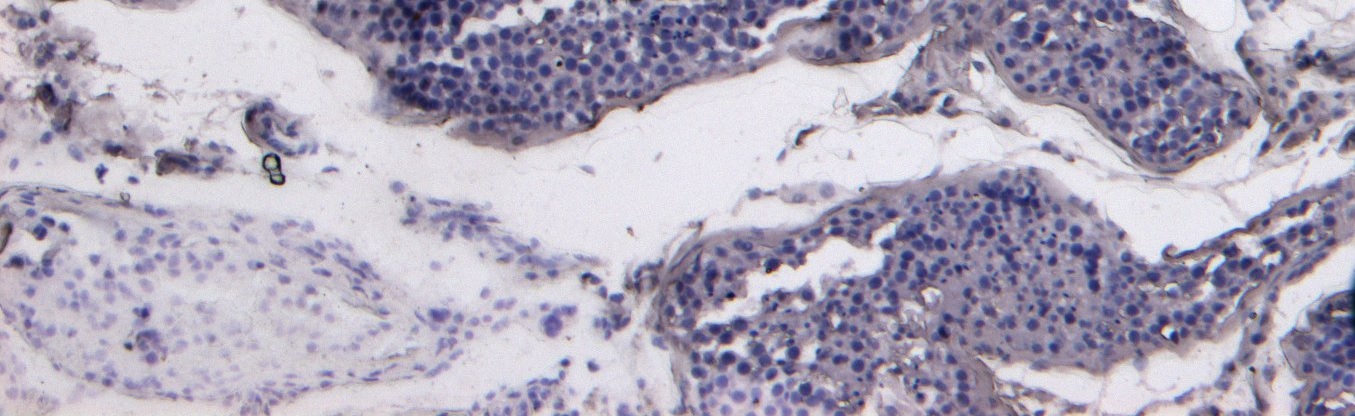

IHC Results Paraffin embedded Human Testis. Recommended concentration: 8µg/ml. A customer reported weak staining on paraffin embedded Human Kidney, at a concentration of 5ug/ml. | |